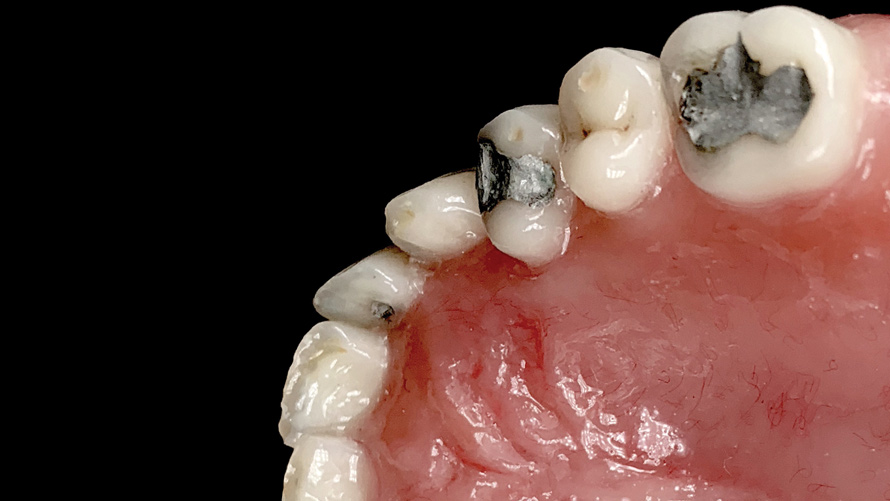

(12. and 13.) Intraoral photographs taken with a smartphone and an EALS device for orthodontic evaluation.

Figure 12

Figure 13

One of the main advantages that smartphone cameras have over DSLR cameras is that nearly everyone is already very familiar with the technology; therefore, the incorporation of these devices into everyday practice does not require learning a new and unfamiliar skill set. The task of producing a series of high-quality clinical photographs for routine examinations (Figure 8), esthetic treatment planning (Figure 9 through Figure 11), or specialty care (Figure 12 and Figure 13) can be delegated with confidence to any staff member during the patient's initial office visit and will generally require less than 5 minutes of time to complete. When a DSLR camera is used, evaluation of the intraoral images either takes place on the small viewfinder built into the camera or necessitates the physical removal of the memory card from the camera to downloaded the images onto a computer for review. An added bonus of smartphone dental photography is that the phone's screen now replaces the much smaller viewfinder of a DSLR camera and provides the clinician with the ability to view and zoom into the patient images on a 5- to 6-inch, high-definition display.